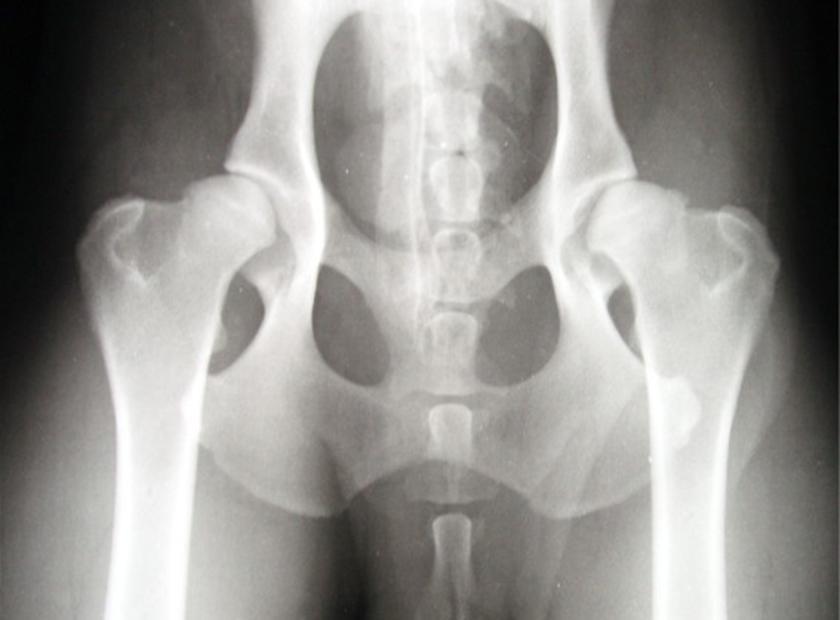

- Gelenksdyplasien wie HD, ED

Beim orthopädischen und vor allem beim Arthrosepatienten steht die Schmerzreduktion im Vordergrund. Außerdem ist es wichtig durch gezielten Muskelaufbau die betroffenen Gelenke zu stabilisieren und die verhärtete Muskulatur der anderen Gliedmaßen / des Rückens zu entlasten.